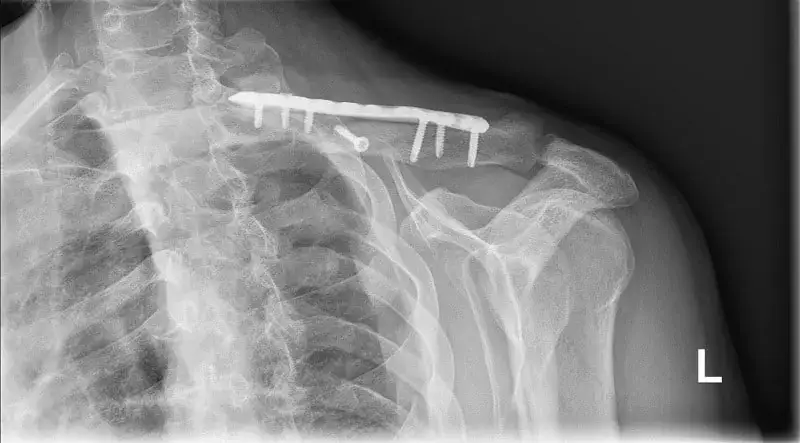

Ile czasu trwa rehabilitacja po złamaniu? Dowiedz się, jakie czynniki wpływają na czas powrotu do zdrowia i jak efektywnie wspierać proces rehabilitacji.